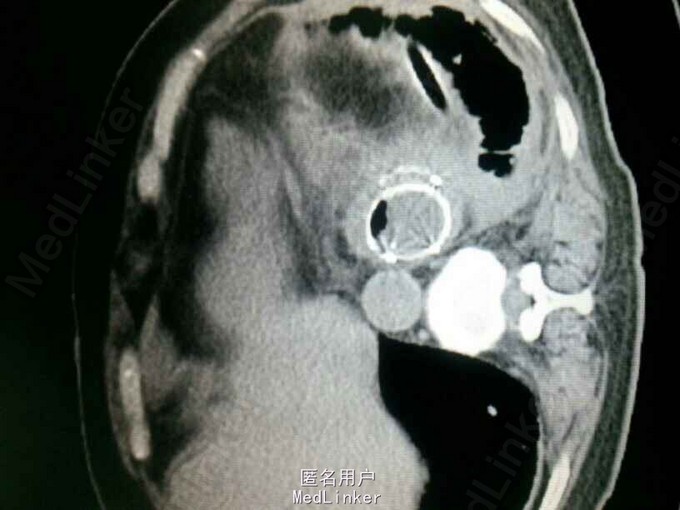

查体:气管居中,左肺呼吸音弱,右肺呼吸音尚可。未闻及湿啰音。胸腔引流管可见褐色浑浊液体引出。 腹部CT肝脾胰未见异常,胆总管扩张。 食管造影:食管下端撕裂,食管胸膜瘘。 胸CT左肺气胸,左侧胸腔内高密度影,考虑造影剂漏入胸腔。左肺实变,右侧少量胸腔积液。

诊断:自发性食管破裂。 治疗:急诊行胸腔闭式引流。后行左剖胸食管破裂修补。术中见胸腔污染严重,见菜叶,消化液等。后纵膈可见较多脓性分泌物,食物残渣,坏死组织。食管裂口处上方可见5cm纵向肌层及粘膜层撕裂口,相应位置处可见纵膈胸膜撕裂口。术后予肠内肠外营养,舒普深,泰能,稳可信,抗感染,术后反复行2次食管造影,仍存在食管破裂口,术后一月行胃镜及食管支架植入术。第二天行进食流质及半流质通畅,平稳出院。